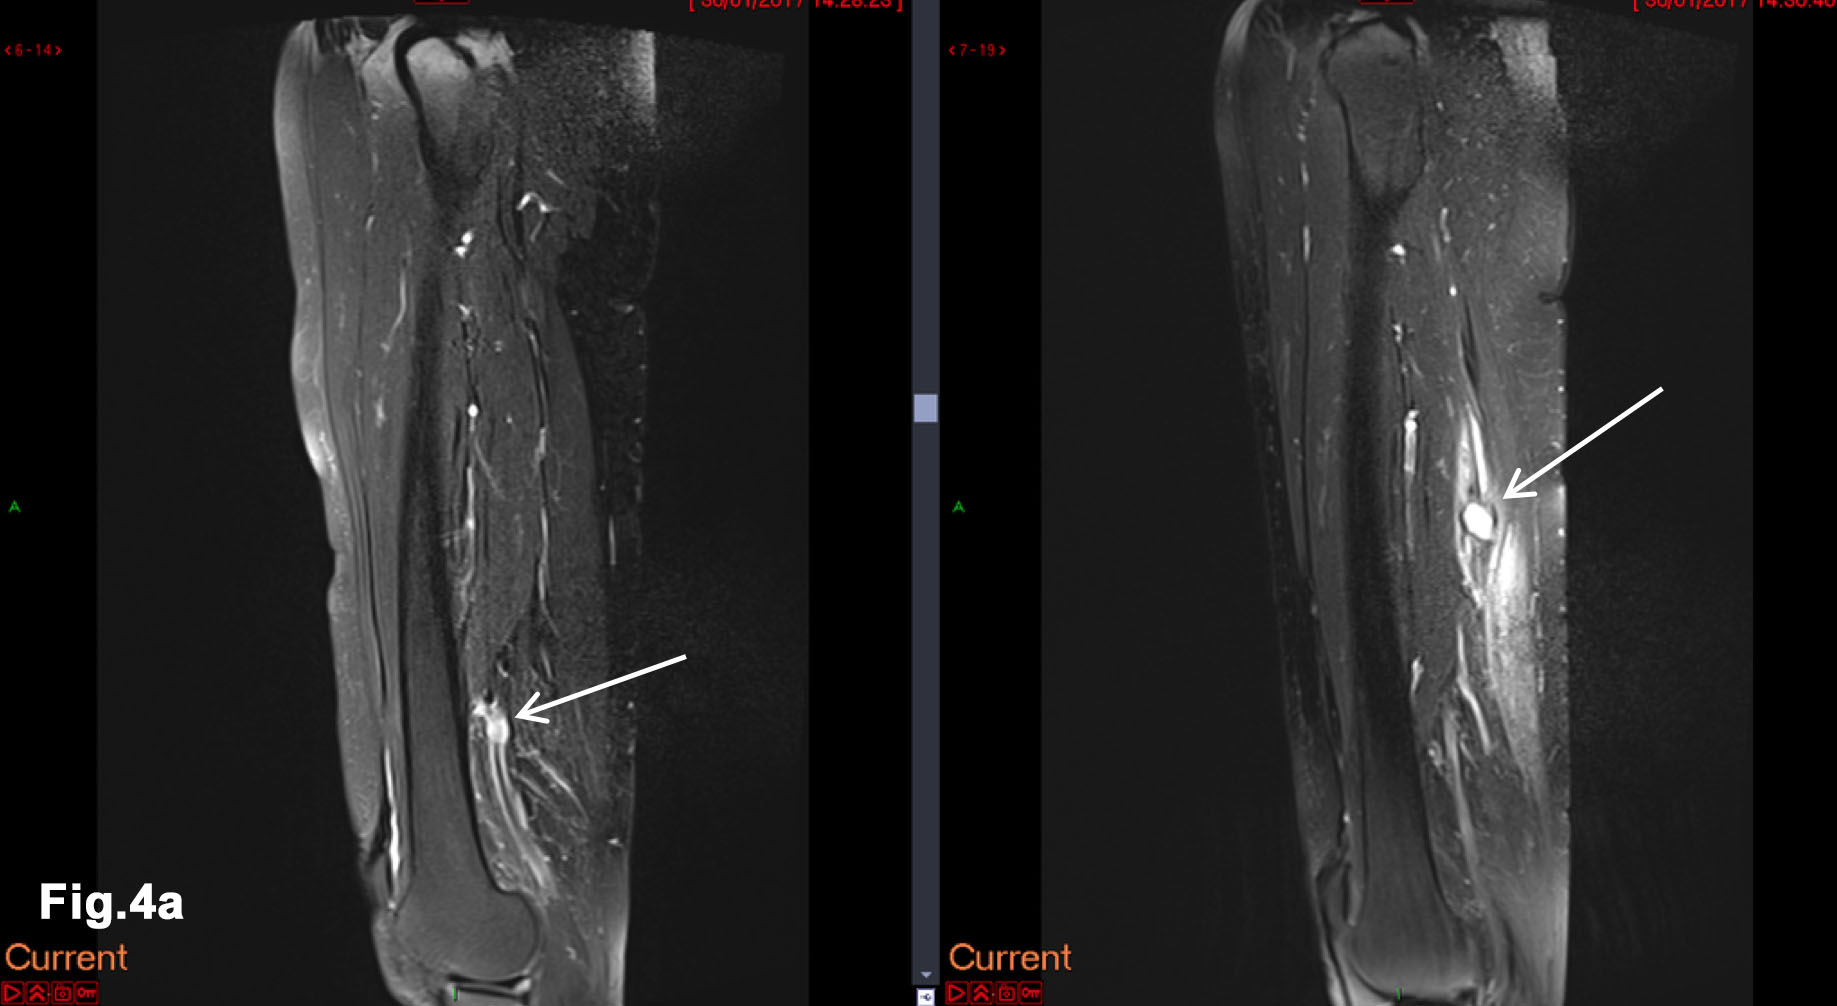

Figure 5 – New presentation of left calf pain with clinical suspicion of a deep venous thrombosis(DVT) – US demonstrated a well-defined hypoechoic mass lesion (a)with moderate vascularity (b) in left gastrocnemius. - Hypoechoic lesion in L gastrocnemius (Fig 5a) - Vascularity demonstrated on Microflow Imaging. (Fig 5b)

- Recent Ultrasound 2018 (Figure 5)

- There was an irregular mass in the left gastrocnemius at the site of tenderness. It was moderately vascular and was subsequently biopsied to reveal a new metastatic deposit similar to the previous lesions and thus disease progression.